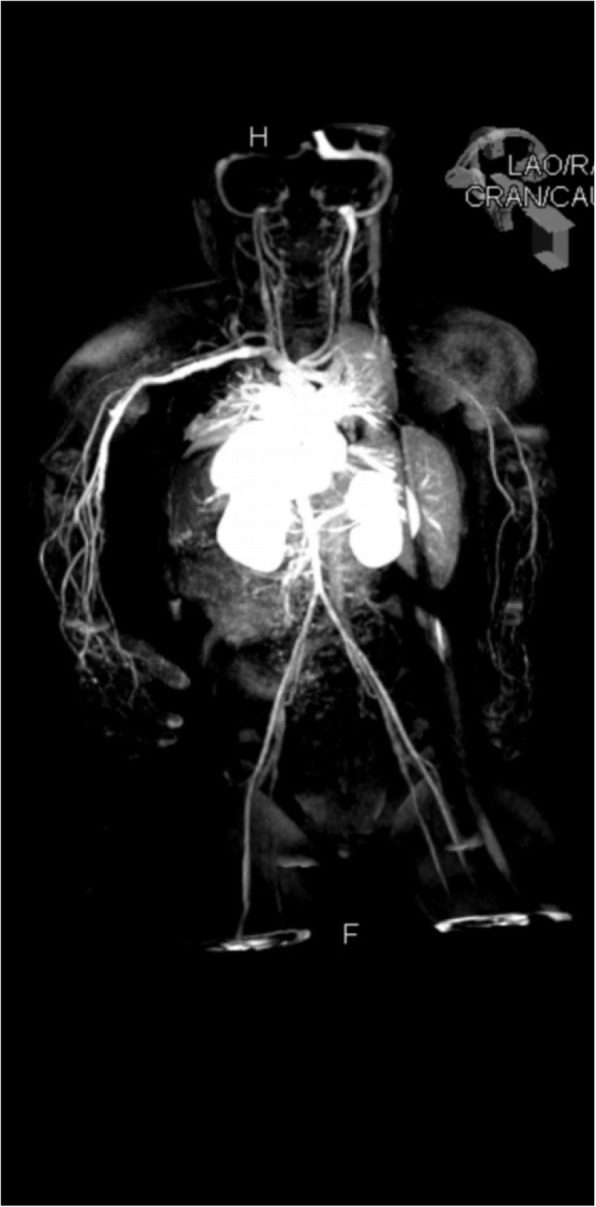

Oral prednisolone was continued with improvement of the discoloration in the infant’s hands and feet, however the left index finger discoloration persisted with progression to necrosis. A diagnostic biopsy was considered but was deferred due to the necrosis and likely low diagnostic yield. Enoxaparin was discontinued at 3 months of age. The male infant was effectively weaned off steroids by 5 months of age, he is now 4 years old with normal growth and development. A follow up image of the hand at 21 months old is shown in Fig. 3. Repeat MRA at 17 months of age showed residual mild tortuosity of the upper extremity abnormalities with no gadolinium enhancement and the lower limbs arteries normal in appearance with normalization of prior tortuosities (Fig. 4).

Fig. 4.

Follow-up magnetic resonance angiography at 17 months of age demonstrates residual tortuosity of forearm vessels with normalization of lower extremity abnormalities and no gadolinium enhancement